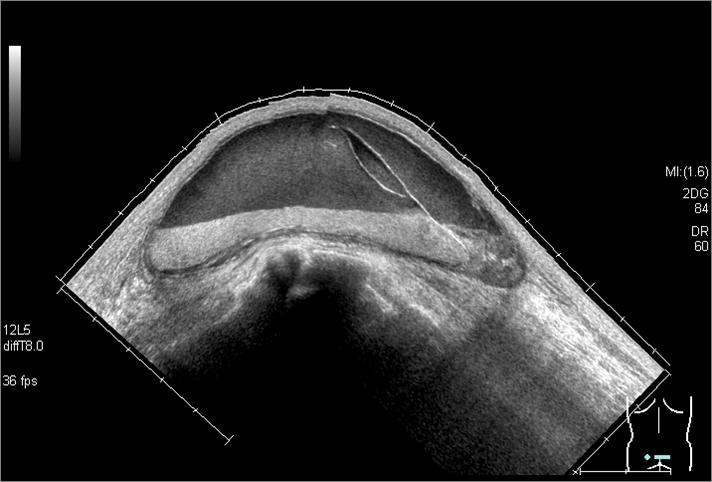

JSS37 大会長賞

氏 名 : 中谷 穏

所 属 : 独立行政法人国立病院機構 水戸医療センター

診断名: 『血 腫』

装 置 : 東芝AplioXG 8.0MHzリニアプローブ

対 象 : 40歳代女性

コメント:突出している病変のため、プローブの両端が浮いてしまいがち。WATER BAGを用いることにより、

両端が浮かなくなり、良質な画像が得られる。腫瘤の深部にあるエコー輝度の高い層は、

体位変動により重力方向に移動した。血球成分の多い部分が反映されているもの判断した。 |